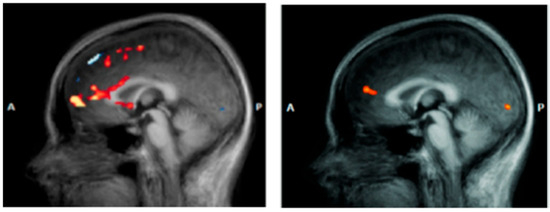

Prefrontal Cortex (DLPFC/VMPFC). The prefrontal cortex (PFC) represents the most consistently altered neural substrate in DS, with convergent evidence spanning over two decades of neurobiological research. The pattern of alterations specifically involves hypoactivation of the dorsolateral prefrontal cortex (DLPFC) and dysfunction of the ventromedial prefrontal cortex (VMPFC), creating functional compromises that correlate directly with depressive symptomatology. Meta-analytic evidence reveals widespread structural reductions in prefrontal regions in DS, with the left DLPFC showing 15–25% reductions in metabolic activity compared to healthy controls [53]. This hypoactivation becomes particularly evident during working memory, executive control, and cognitive emotion regulation tasks, manifesting through reduced cerebral perfusion and decreased glucose metabolism [54,55]. Functional magnetic resonance imaging studies have documented specific alterations in connectivity between the DLPFC and frontoparietal network, with 30–40% reductions in neural synchronization during complex cognitive tasks. These dysfunctions correlate significantly with neuropsychological assessments of executive functions, sustained attention, and working memory, providing a neurobiological foundation for the cognitive symptoms commonly observed in DS [56]. The VMPFC presents complementary alterations, characterized by anomalous hyperactivation during negative emotional stimulus processing and hypoactivation during voluntary emotional regulation tasks [57]. This pattern reflects a 35–50% compromise in top-down modulation effectiveness of limbic structures (Figure 2), determining reduced cognitive control over emotional responses [58]. The therapeutic implications of prefrontal dysfunction have been particularly well-demonstrated through repetitive transcranial magnetic stimulation (rTMS) research. High-frequency stimulation of the left DLPFC has shown robust antidepressant effects, with accelerated protocols achieving 60–75% remission rates in treatment-resistant patients [59]. The identification of specific connectivity profiles between stimulation sites and the subgenual anterior cingulate cortex has further refined targeting strategies, demonstrating how understanding neural correlates can directly inform therapeutic approaches [60].

Figure 2.

Major depressive disorder: new clinical, neurobiological, and treatment perspectives [61].